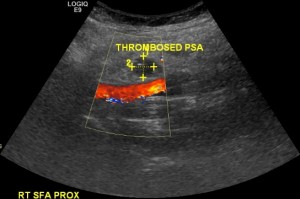

On the day post ablation Ms. X started complaining of groin tenderness. Examination revealed a preserved femoral pulse and a faint bruit that was not noted before. A groin ultrasound was ordered. The main finding is seen in the image below:

This is a pseudoaneurysm. There is a typical to and fro flow pattern in the neck. There is a typical ‘bubble’ with a ‘Yin-Yang’ flow pattern. This pseudoaneurysm measured about 1.2 cm. What would you do in this case?